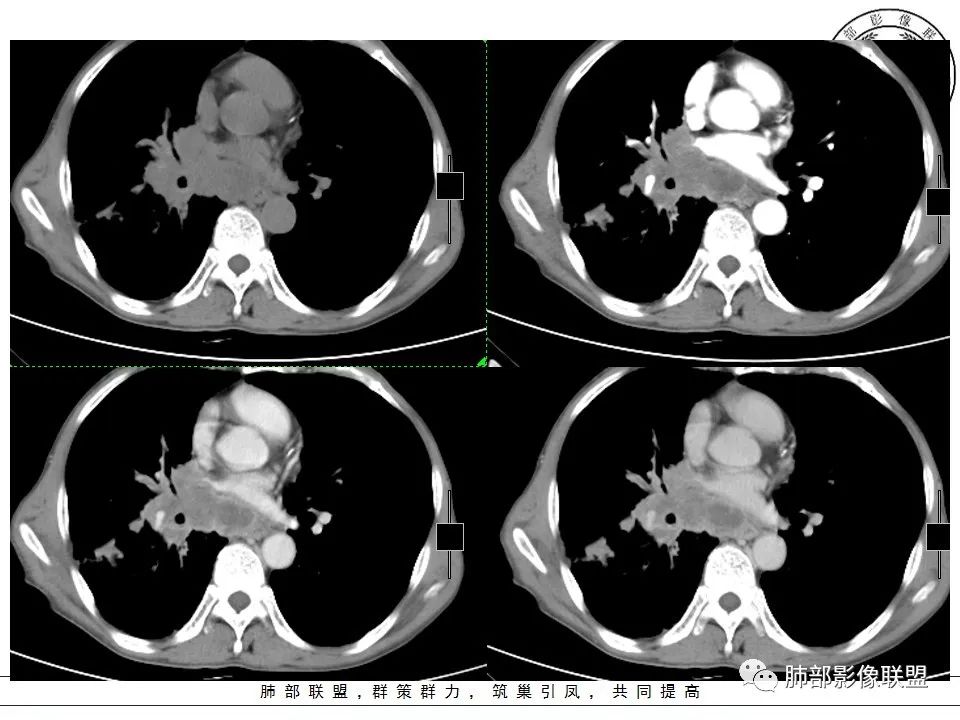

右下肺外后基底段不规则实变,其周散在GG0,边界清楚,病灶由外朝内蔓延,包埋相应支气管,整体体积未见减小,坏死区不彻底较模糊,其间可见穿行血管受侵僵直、弯曲,纵隔及右肺门淋巴结肿大融合坏死,老年男性,慢性病程,反复咳嗽,抗炎效果不佳,考虑恶性肿瘤,以低分化腺癌可能。| 医学百科网 | YxBaike.Com

右肺下叶不规则肿块,周围大片状磨玻璃,支气管远端堵塞,见条形粘液栓低密度影,增强扫描不均匀强化,血管造影征,粘液栓延迟强化,右肺门、纵隔淋巴结肿大融合,环形强化,边界清,右中间段、中下叶支气管狭窄,右下肺静脉细小;老年男性,慢性病程,肺气肿背景,吸烟史,抗感染治疗效果不佳,考虑恶性,小细胞肺癌?低分化腺癌?肺内病灶与右肺门、纵隔淋巴结强化不符合,还需与结核鉴别,不排外2元论! 医学百科网 | YxBaike.Com

患者老年男性,反复咳嗽半年余。抗感染治疗效果欠佳。胸部CT:右肺下叶大片实变占位影,沿支气管走行,形态不规则,密度不均,其内可见低密度粘液栓,血管造影征,肺门侧支气管血管束增粗,支气管管腔狭窄,支气管进入病灶堵塞,胸膜牵拉,周围大片磨玻璃影,小叶间隔增厚,斜裂多发结节,胸膜不规则增厚,胸腔少量积液,纵膈多发淋巴结肿大并融合,且内见低密度区,环形强化,综合考虑恶性病变,腺癌可能性大。鉴别结核。 医学百科网 | YxBaike.Com

双肺胸膜下肺气肿,右肺肺门及中下叶肿块,形态不规则中叶病灶包绕支气管生长,支气管略狭窄,下叶支气管似有堵塞,病变内密度不均匀,平扫可见低密度坏死,增强后可见环形不均匀强化,有血管穿行,病灶边缘彭隆,分叶、毛刺,牵拉胸膜,胸膜下有少量胸水,胸膜不光滑,有结节感,纵隔淋巴结肿大并环形不均匀强化,中年男性,有大量吸烟史,考虑恶性:小细胞癌,鳞癌,鉴别放线菌 医学百科网 | YxBaike.Com

右肺下叶后基底段不规则软组织肿块,呈轻度膨胀改变,边缘可见蠕虫样凸起,肿块沿支气管向肺门侵犯,致右肺下叶支气管开口变窄,周围见软组织肿块,纵隔多组淋巴结肿大,增强扫描肿块不均匀强化呈“沼泽样”改变,其内穿行血管变细,肺门及纵隔呈“冰冻样”改变,综上所述符合小细胞肺癌影像学表现。

老年男性,以咳嗽半年为主诉,曾给予抗感染治疗效果欠佳。胸部影像示纵隔及右肺门淋巴结肿大,右肺下叶占位性病变,并周围大片状磨玻璃影。增强扫描纵隔淋巴结呈环形强化,内部坏死明显边界清楚,淋巴结粘连融合。右肺下叶肿块增强扫描内部坏死明显,支气管远端截断,延迟强化。考虑慢性感染性疾病,如放线菌,奴卡菌。与腺癌并转移鉴别。

老年男性,吸烟,肺气肿背景。右肺门及下叶不规则肿物,内部沼泽样强化,血管包埋挤压,纵隔淋巴结肿大融合,周围脂肪间隙显示。考虑小细胞肺癌。

老年男性,反复咳嗽半年,体重下降20公斤。吸烟指数2000(50×40), 影像表现:肺气肿背景,右肺下叶斑片状实变影,内部支气管部分扭曲稍扩张,周围广泛小叶间隔增厚伴结节状改变,中间部分小叶间内间隔增厚,呈细网格征,远端阻塞形成空气潴瘤征,增强后呈斑片状不规则坏死,少部分血管破坏,多数血管走行较好。纵隔内淋巴结广泛肿大,坏死,呈环状稍强化,部分呈薄环状改变,部分环较厚。1、综合分析:疾病谱,肺炎型肺癌,肺结核,淋巴瘤,结节病。2、初步考虑肺炎型肺癌可能(鳞癌>腺癌),鳞癌支持点:老年男性,长期吸烟史,肺气肿背景,远端阻塞性空气潴留,实变区中间坏死,支气管扩张扭曲,纵隔淋巴结坏死。鳞癌不支持点:实片区坏死不够彻底,非典型湖泊样坏死,中间多数血管走行较自然。鳞癌淋巴结转移相对更少见一些。腺癌支持点:实变区坏死情况及淋巴结表现以及癌淋形成支持。腺癌不支持点:老年男性,长期吸烟史,肺气肿背影,远端阻塞性空气潴留。鉴别诊断:1、肺结核,反复咳嗽半年,体重减轻20斤支持,淋巴结环形强化,尤其是部分呈薄环形强化支持,但无结核中毒症状,坏死不彻底不支持,纵隔淋巴结部分壁不均匀,不支持。所以结核可能性较小。2、淋巴瘤,纵隔淋巴结广泛增大及实变区部分血管走行较自然支持。实变区坏死及部分血管有部分不支持,淋巴结坏死不支持。所以可能性也不大。

患者老年男性,慢性病程,干咳,无痰,既往有大量吸烟史。胸CT:右肺下叶支气管明显狭窄,右肺下叶外后基底段占位性病变,病灶周围可见毛玻璃样渗出影及肺气肿。增强纵膈窗可见:右肺下叶实性占位病灶内可见低密度区,并可见血管造影正,2R 4R 4L 7及右肺门淋巴结明显肿大,部分肿大淋巴结可见融合坏死。

综合考虑患者为恶性病变———腺癌?

老年男性,不良吸烟史慢性病程,干咳半年,抗感染无效,影像:双肺胸膜下旁间隔气肿,右肺下叶大块样实变,有占位效应,胸廓无缩小,彭隆分叶,胸膜增厚牵拉凹陷,周围磨玻璃影边界不清,小叶间隔增厚,斜裂受累有结节感,支气管截断,近端环形狭窄,纵膈窗提示不均匀延迟强化,坏死粘液栓,累及血管纤细,远端伴有蜂窝,双侧肺门、纵膈、多组淋巴结肿大,融合,中央坏死环形强化,上腔静脉受压,考虑恶性可能性大,腺癌? 医学百科网 | YxBaike.Com

需要与淋巴瘤鉴别,影像有淋巴组织增殖样改变,有血管漂浮,周围小叶间隔厚,但坏死居多,另需要与结核鉴别:淋巴结有环形坏死特点,支气管深达近端,粘液栓,有结核肉芽肿可能,确诊还需要活检一锤定音

老年男性,咳嗽半年,体重减轻20斤。右肺下叶肿块,与增大的右肺门境界不清,形态不规则,强化密度不均,病灶内见条状粘液栓及低密度坏死区,坏死区内血管破坏不明显,纵隔肺门淋巴结增大、大部分环形强化,内见坏死区,内壁光整。周围磨玻璃影,间质增厚。右侧少量胸腔积液。双侧肺气肿背景。综合考虑恶性病变,淋巴瘤?鉴别结核。

老年男性,干咳半年。右肺门及纵隔淋巴结肿大,内部不均匀坏死,无坏死区可见强化,符合恶性转移性淋巴结,左肺门无明显淋巴结肿大,考虑跟右下肺病变相关。右下肺肿块,边缘膨隆,近端支气管见鼠尾状截断,内见支气管粘液栓,周围见斑片状影及牵拉性改变,周围间质增厚。综上,考虑右肺下叶恶性肿瘤(腺癌)并右肺门、纵隔淋巴结转移,粘液腺癌可能性大。

男,67岁,反复咳嗽半年。右下叶磨玻璃影背景见团块影,部分边缘膨隆,部分平直,似有分叶,近端支气管狭窄,增强有强化,内有条状低密度灶(粘液栓?),血管稍变小,走形尚正常。纵隔多发环形强化的肿大淋巴结。考虑:1.淋巴瘤,依据:病灶内似有血管漂浮,纵隔多发肿大淋巴结。2.肺癌,依据:肿块状病灶,部分边缘膨隆、分叶,近端支气管狭窄。3.肺结核,依据:结核是妖。

老年男性,有大量吸烟史,反复咳嗽半年。纵隔及肺门多发肿大淋巴结,多发融合并有坏死,坏死边界清,各级支气管外压性狭窄,右肺下叶大肿块,内有多灶性坏死,外周有磨玻璃影,伴蜂窝状改变,中度强化,局部胸膜肥厚有少量胸腔积液。考虑恶性肿瘤,腺癌可能性大,鉴别淋巴瘤,结核? 医学百科网 | YxBaike.Com

右肺下叶见一厚壁偏心空洞,周围广泛小叶间隔增厚伴结节状改变,胸膜栽赃征,考虑恶性。

老年男性。病史半年,1月前就发现有占位,可惜没旧片对比,体重减轻20斤。病史提示病史长,占位性病变,恶性可能。淋巴结肿大明显,淋巴结的特点是坏死、融合、偏侧,坏死有残留。淋巴瘤不太支持,淋巴瘤坏死这么明显的比较少,前纵隔的可以,其他区域的淋巴瘤坏死这么彻底的罕见,放待排,上次於老师发过一例腹部有,但是毕竟少。淋巴结的改变:结核?类癌?转移瘤?淋巴瘤最后。主病灶一起淋巴结肿大,内有大量粘液坏死,不典型类癌需考虑,结核待排。 医学百科网 | YxBaike.Com

2.右肺下叶大范围磨玻璃密度片影,边界不清,小叶间隔增厚明显,胸膜下区域见气肿。 医学百科网 | YxBaike.Com

3.片影中央见较大块状影,边界可分辨,不规则分叶,未显示毛刺,可见棘突及胸膜牵拉。 医学百科网 | YxBaike.Com

块影密度不均匀,可见明显液化区。明显不均匀环形强化,病灶内血管未见明显异常。

块影明显支气管相关,中间段支气管有狭窄,后段支气管低密度阻塞(局部未强化),未见枯枝征。 医学百科网 | YxBaike.Com

4.后基底段多发小结节影。 医学百科网 | YxBaike.Com

5.右肺门及纵隔见多数明显肿大淋巴结,环形或分隔样强化,这点表现相当显著。